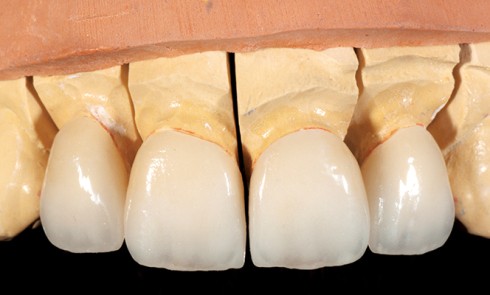

Article réservé à nos abonnés Facettes en céramique et gingivectomies : une approche a minima

Le sourire harmonieux est le fruit d’un équilibre complexe impliquant le positionnement des dents, leur couleur, leur forme et leur...